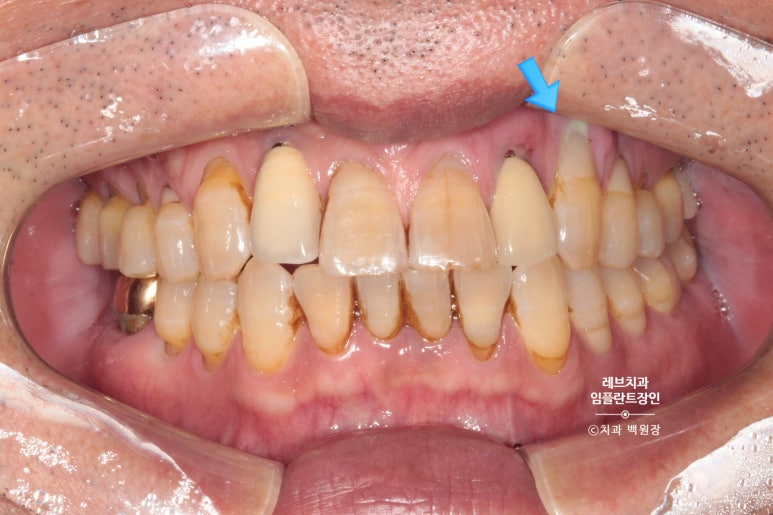

왼쪽 송곳니와 앞니가 흔들리고 고름이 나요.

왼쪽 위 송곳니 (앞니)에서 고름이 나온다는 말씀을 하시던 환자분입니다.

보시면 가만히 있어도 치아와 잇몸 사이에서 고름이 올라오는 것을 보실 수 있어요..

흡연을 좋아하시던 분이었고, 만성 치주염이 심해져서 치주농양까지 진행된 상태입니다.

치과용 파노라마 사진에서도 왼쪽 위 송곳니 주변으로 잇몸뼈가 사라진 것을 보실 수 있는데요,